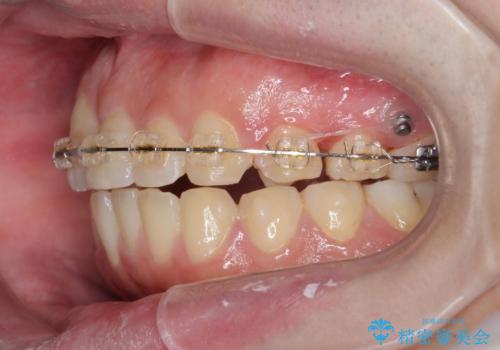

正中過剰埋伏歯で生じた前歯の審美障害 矯正治療での改善

- ワイヤー矯正 → インビザライン

見た目、噛み合わせが大きく改善し、大変喜んでいただくことができました。